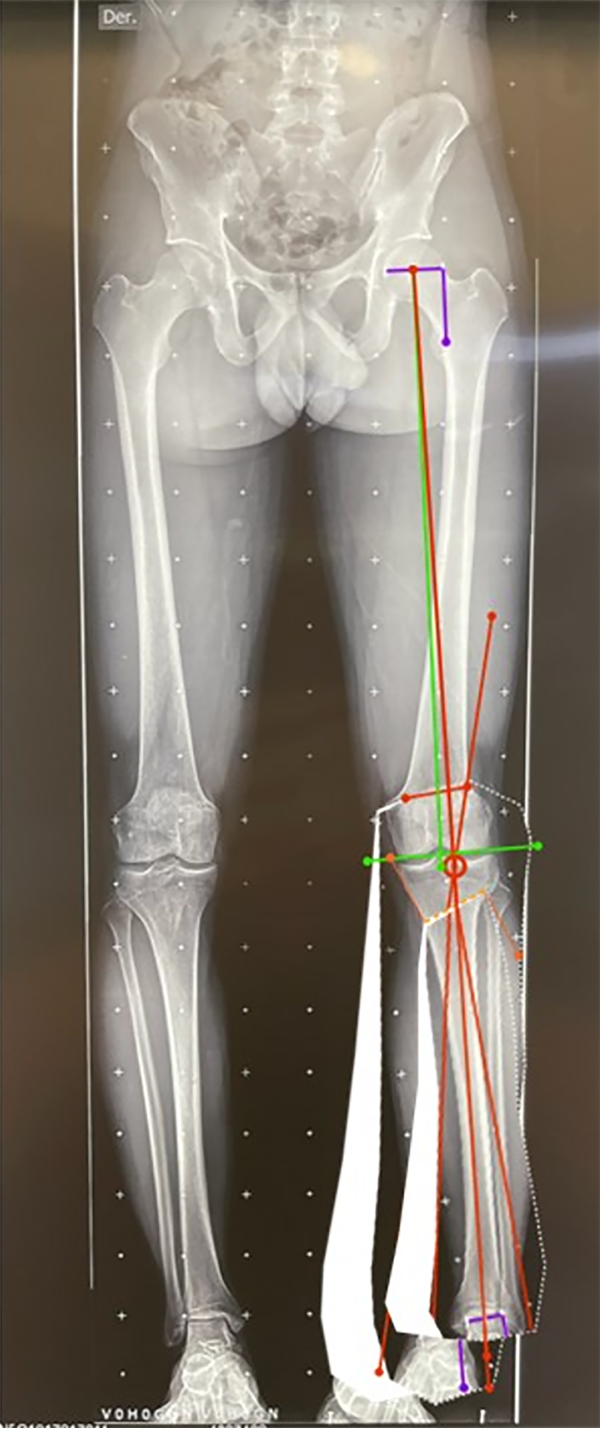

Figura 4: Ángulo femoral distal lateral mecánico (mLFDA): mLDFA y MPTA bilateral, se observa del lado izquierdo una deformidad en varo del fémur 92° (normal 85-90°) y la tibia 84° (normal 85-90°). Lado derecho con una deformidad en varo del fémur 92° y la tibia 87° en valor normal.

Figura 16: Medición del mLDFA y MPTA postcorrección: después del planeamiento de la osteotomía se calcula el mLDFA, en este caso es de 88° (valor normal 85-90°) y el MPTA es de 89° (valor normal 85-90°), considerados ángulos corregidos normales y sin alteración de la línea articular.